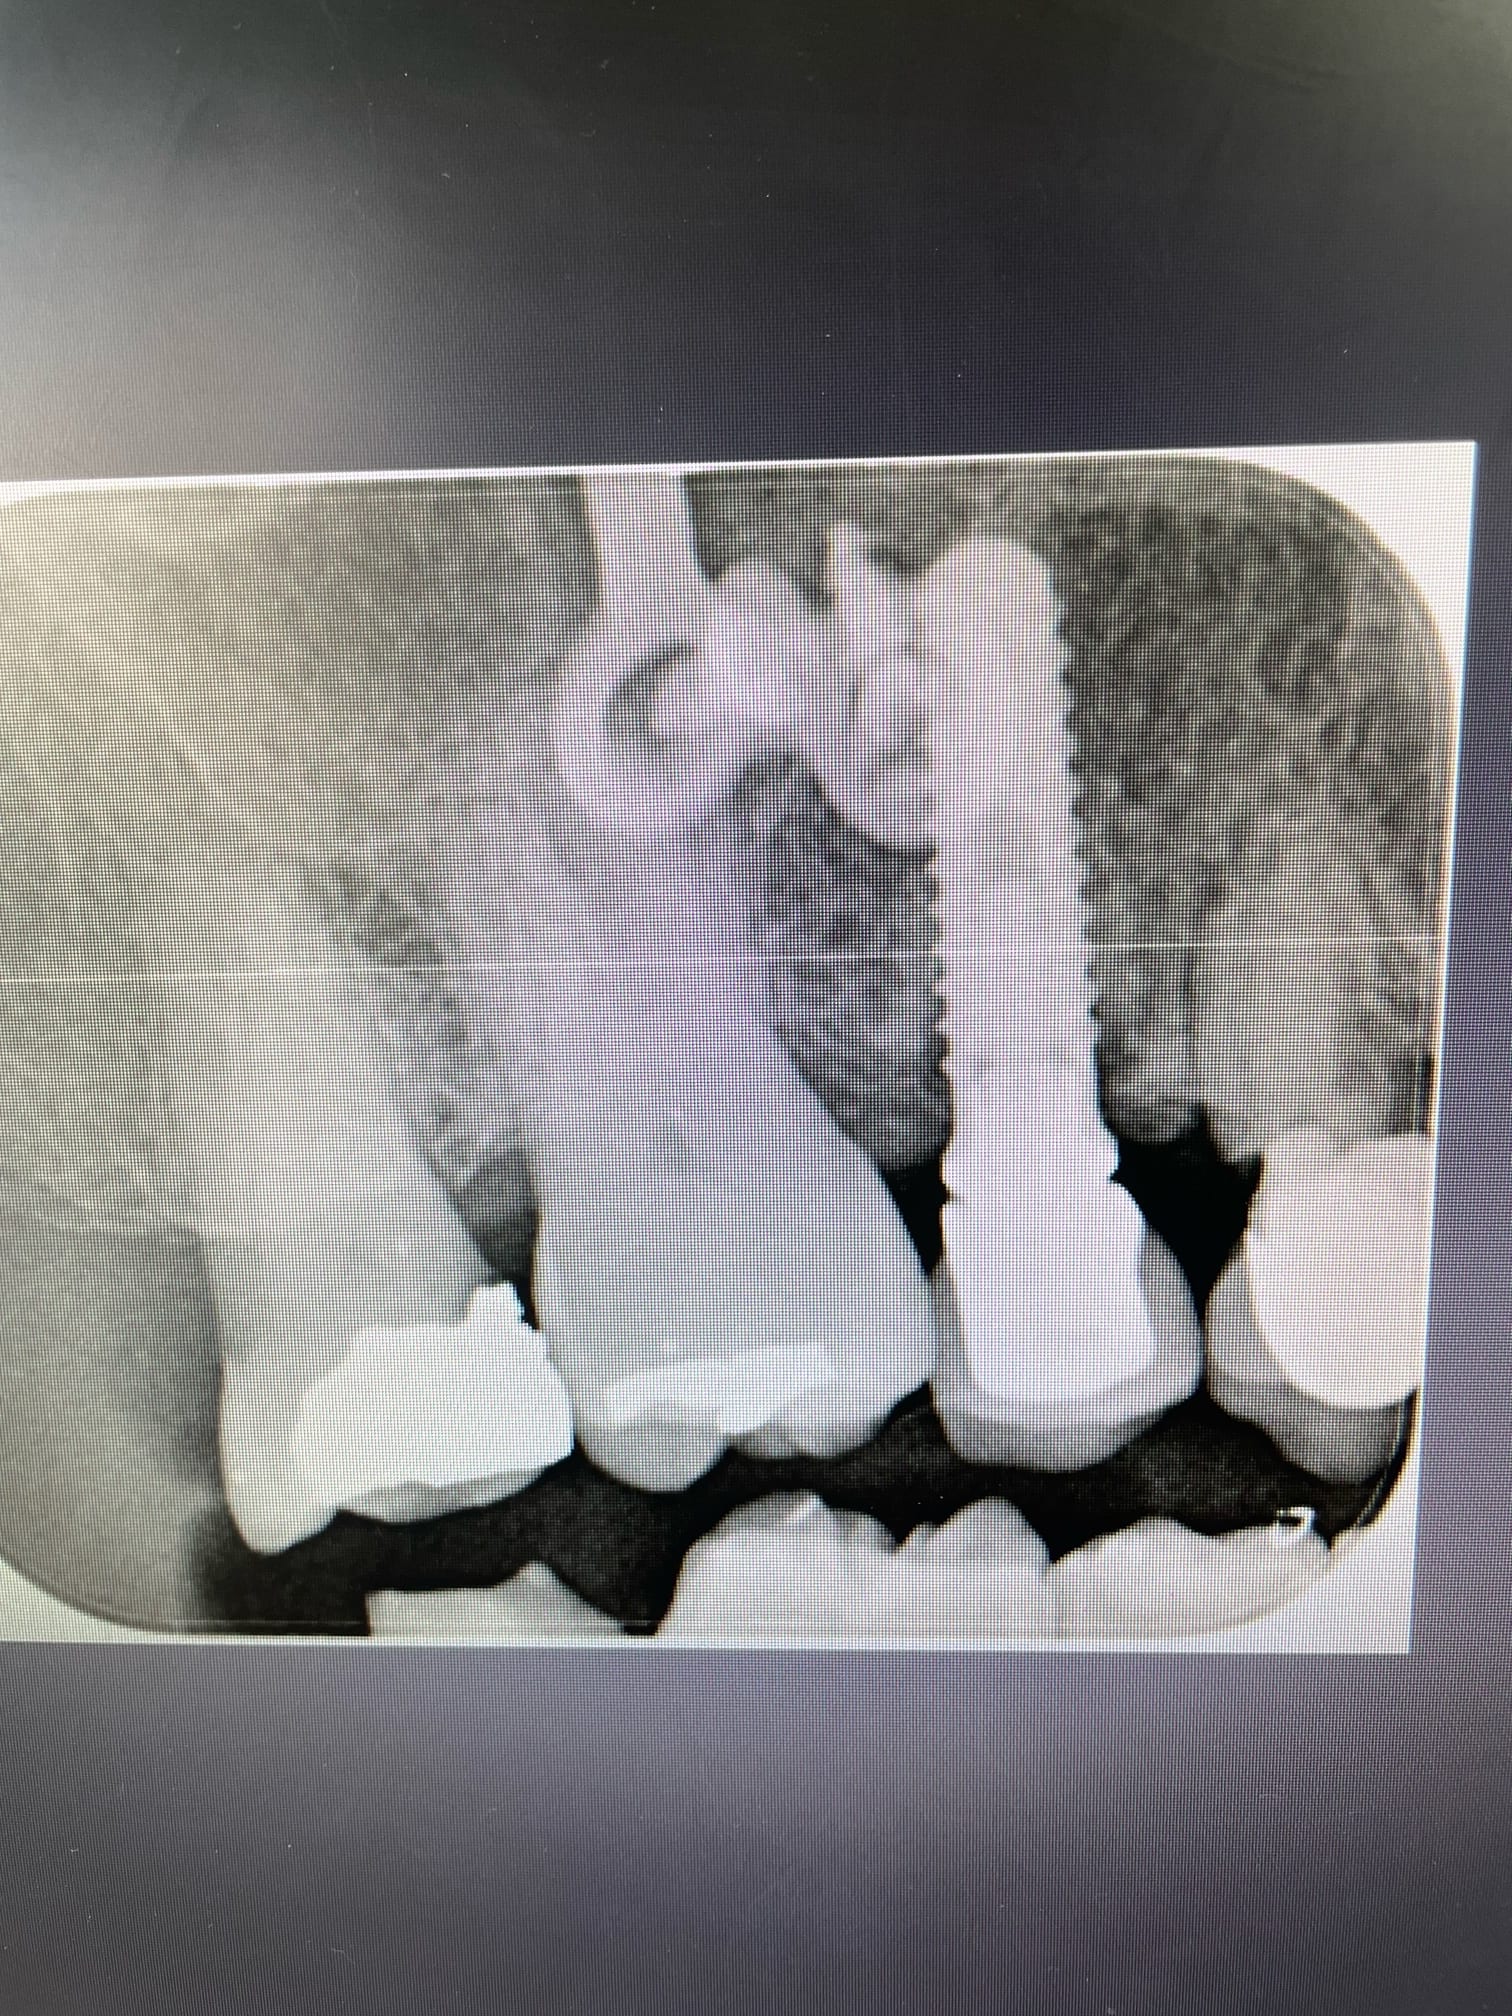

Bonjour, je cherche à confirmer que ces implants sont bien des IDI.

Si oui savez vous avec quelle marque ils sont compatibles et s’il existe des scanbody pour faire de l’empreinte optique?

Pas idi sur . Le seul ressemblant chez idi serait idmax mais il sont different sur plusieurs points

c'est clair.....l'idmax c'est celui qui se rapproche le plus sans cocher toutes les cases....c'est ce qui fait que j'ai pas l'impression que çà soit çà, car les spires semblent différentes.....et pour l'instant, je sèche....

Taille du col et régularité des spires

Des nouvelles de ma galère: les implants sont bien des IDI.

J’ai remis la main sur l’associé du poseur initial. Par contre ce sont des implants qui ont 15 ans. Peut être que la forme a évolué depuis. J’attends la traçabilité exacte la semaine prochaine.

Pour polluer le fil un peu.

Tu vas reprendre les couronnes pour faire un bridge 24/25/26 ou juste à cause de l'adaptation douteuse des couronnes actuelles ?

25 est HS. Mobilité 4 avec une pêche qui flirt dangereusement avec la fixation au dessus. Le bridge est plus simple que d’extraire et espérer récupérer un peu d’os à la cicatrisation. Pour 12 et 15, les ceram sont explosées , à reprendre. ça c’est pour les implants. Pour le reste, ça bruxe version sauvage…les incisives Mand ressemblent à des grains de riz et au max c’est super moche… il est donc prévu une hausse de DV ( aïe aïe aïe ) et une réhabilitation esthétique des blocs antérieurs…

Traçabilité définitive reçue ce matin: IDMAX 4,4. Y a plus qu’à !